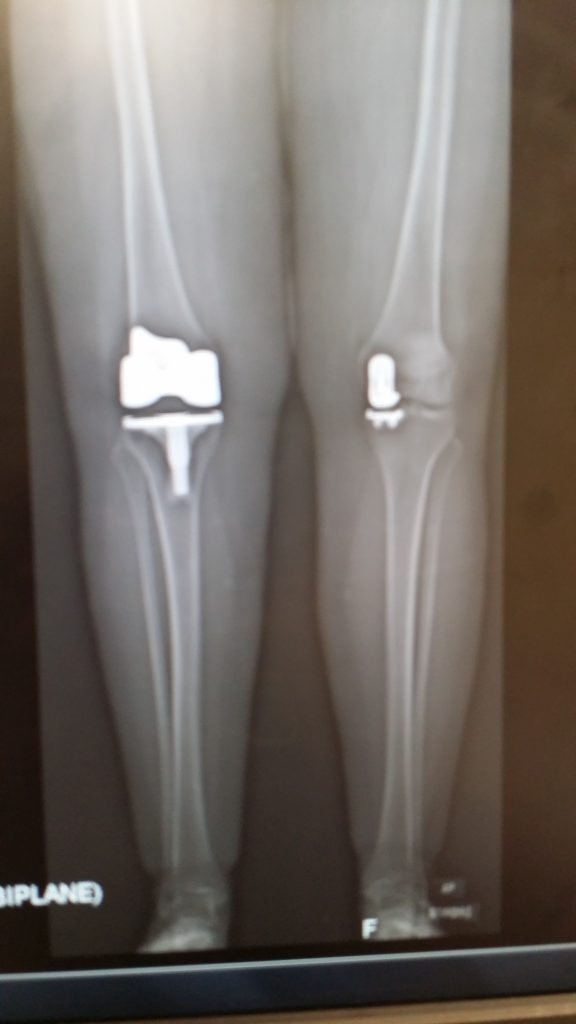

Needless to say, I made the major decision to get my surgeries done at HSS. Not only did I have one knee replacement – I had a Partial Knee Replacement (2014); and went back for a TKR in 2016.